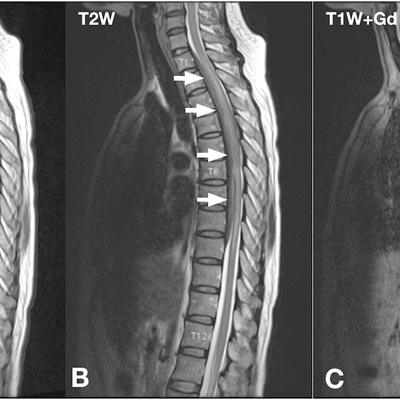

Click on an image below to view more info.